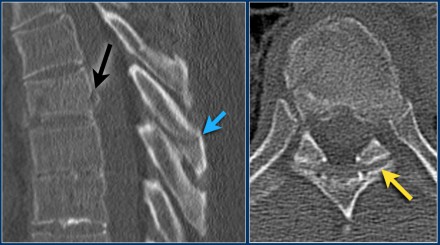

Case 5

Look at the images.

How would you describe the morphology and the PLC?

Then scroll to the next images.

The findings are:

- Morphology: Burst - 2 points

There is retropulsion of a body fragment (black arrow) - PLC: widening of both facet joints (yellow arrow) and a fracture of spinous process (blue arrow) - 3 points

- TLICS based on imaging: 5 points

Discussion: based on only

these two images it is hard to say whether this is burst with

PLC-injury or maybe distraction on the posterior side.

In either case the TLICS-score is high and this patient is a surgical candidate.